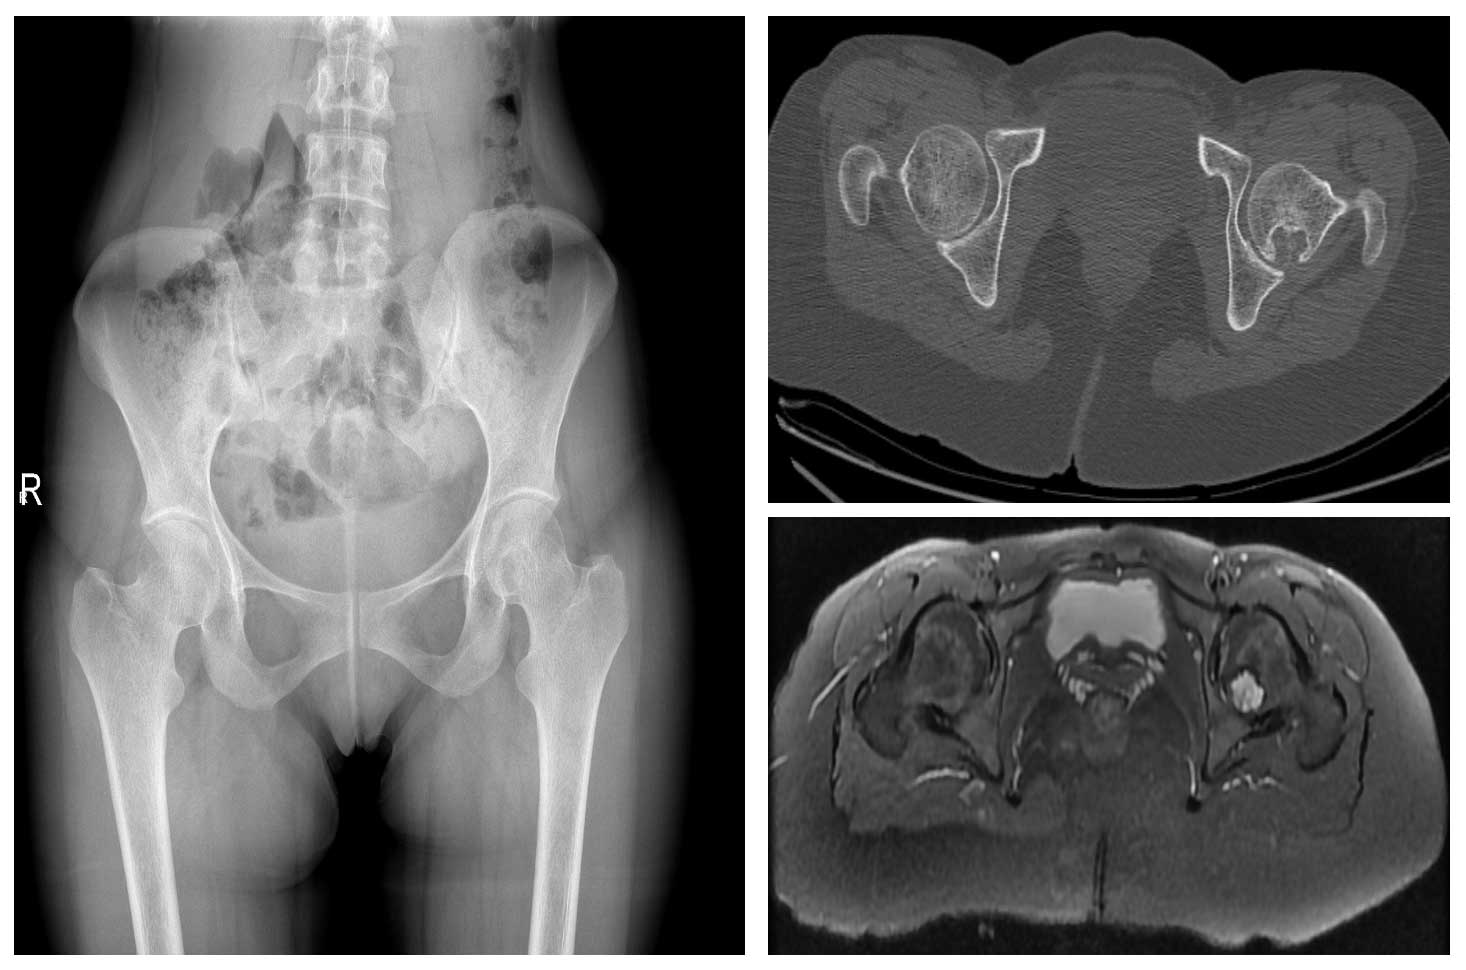

Ameliyat Esnası: Tümörün temizlenmesi ve oluşan boşluğun kemik çimentosu ile doldurulduktan sonra başsız vida ile fiksasyonu görülmekte.

Ameliyat Sonrası: Röntgende tümörün temizlenmesi sonrası oluşan boşluğun kemik çimentosu ile doldurulduktan sonra başsız vida ile fiksasyonu görülmekte.